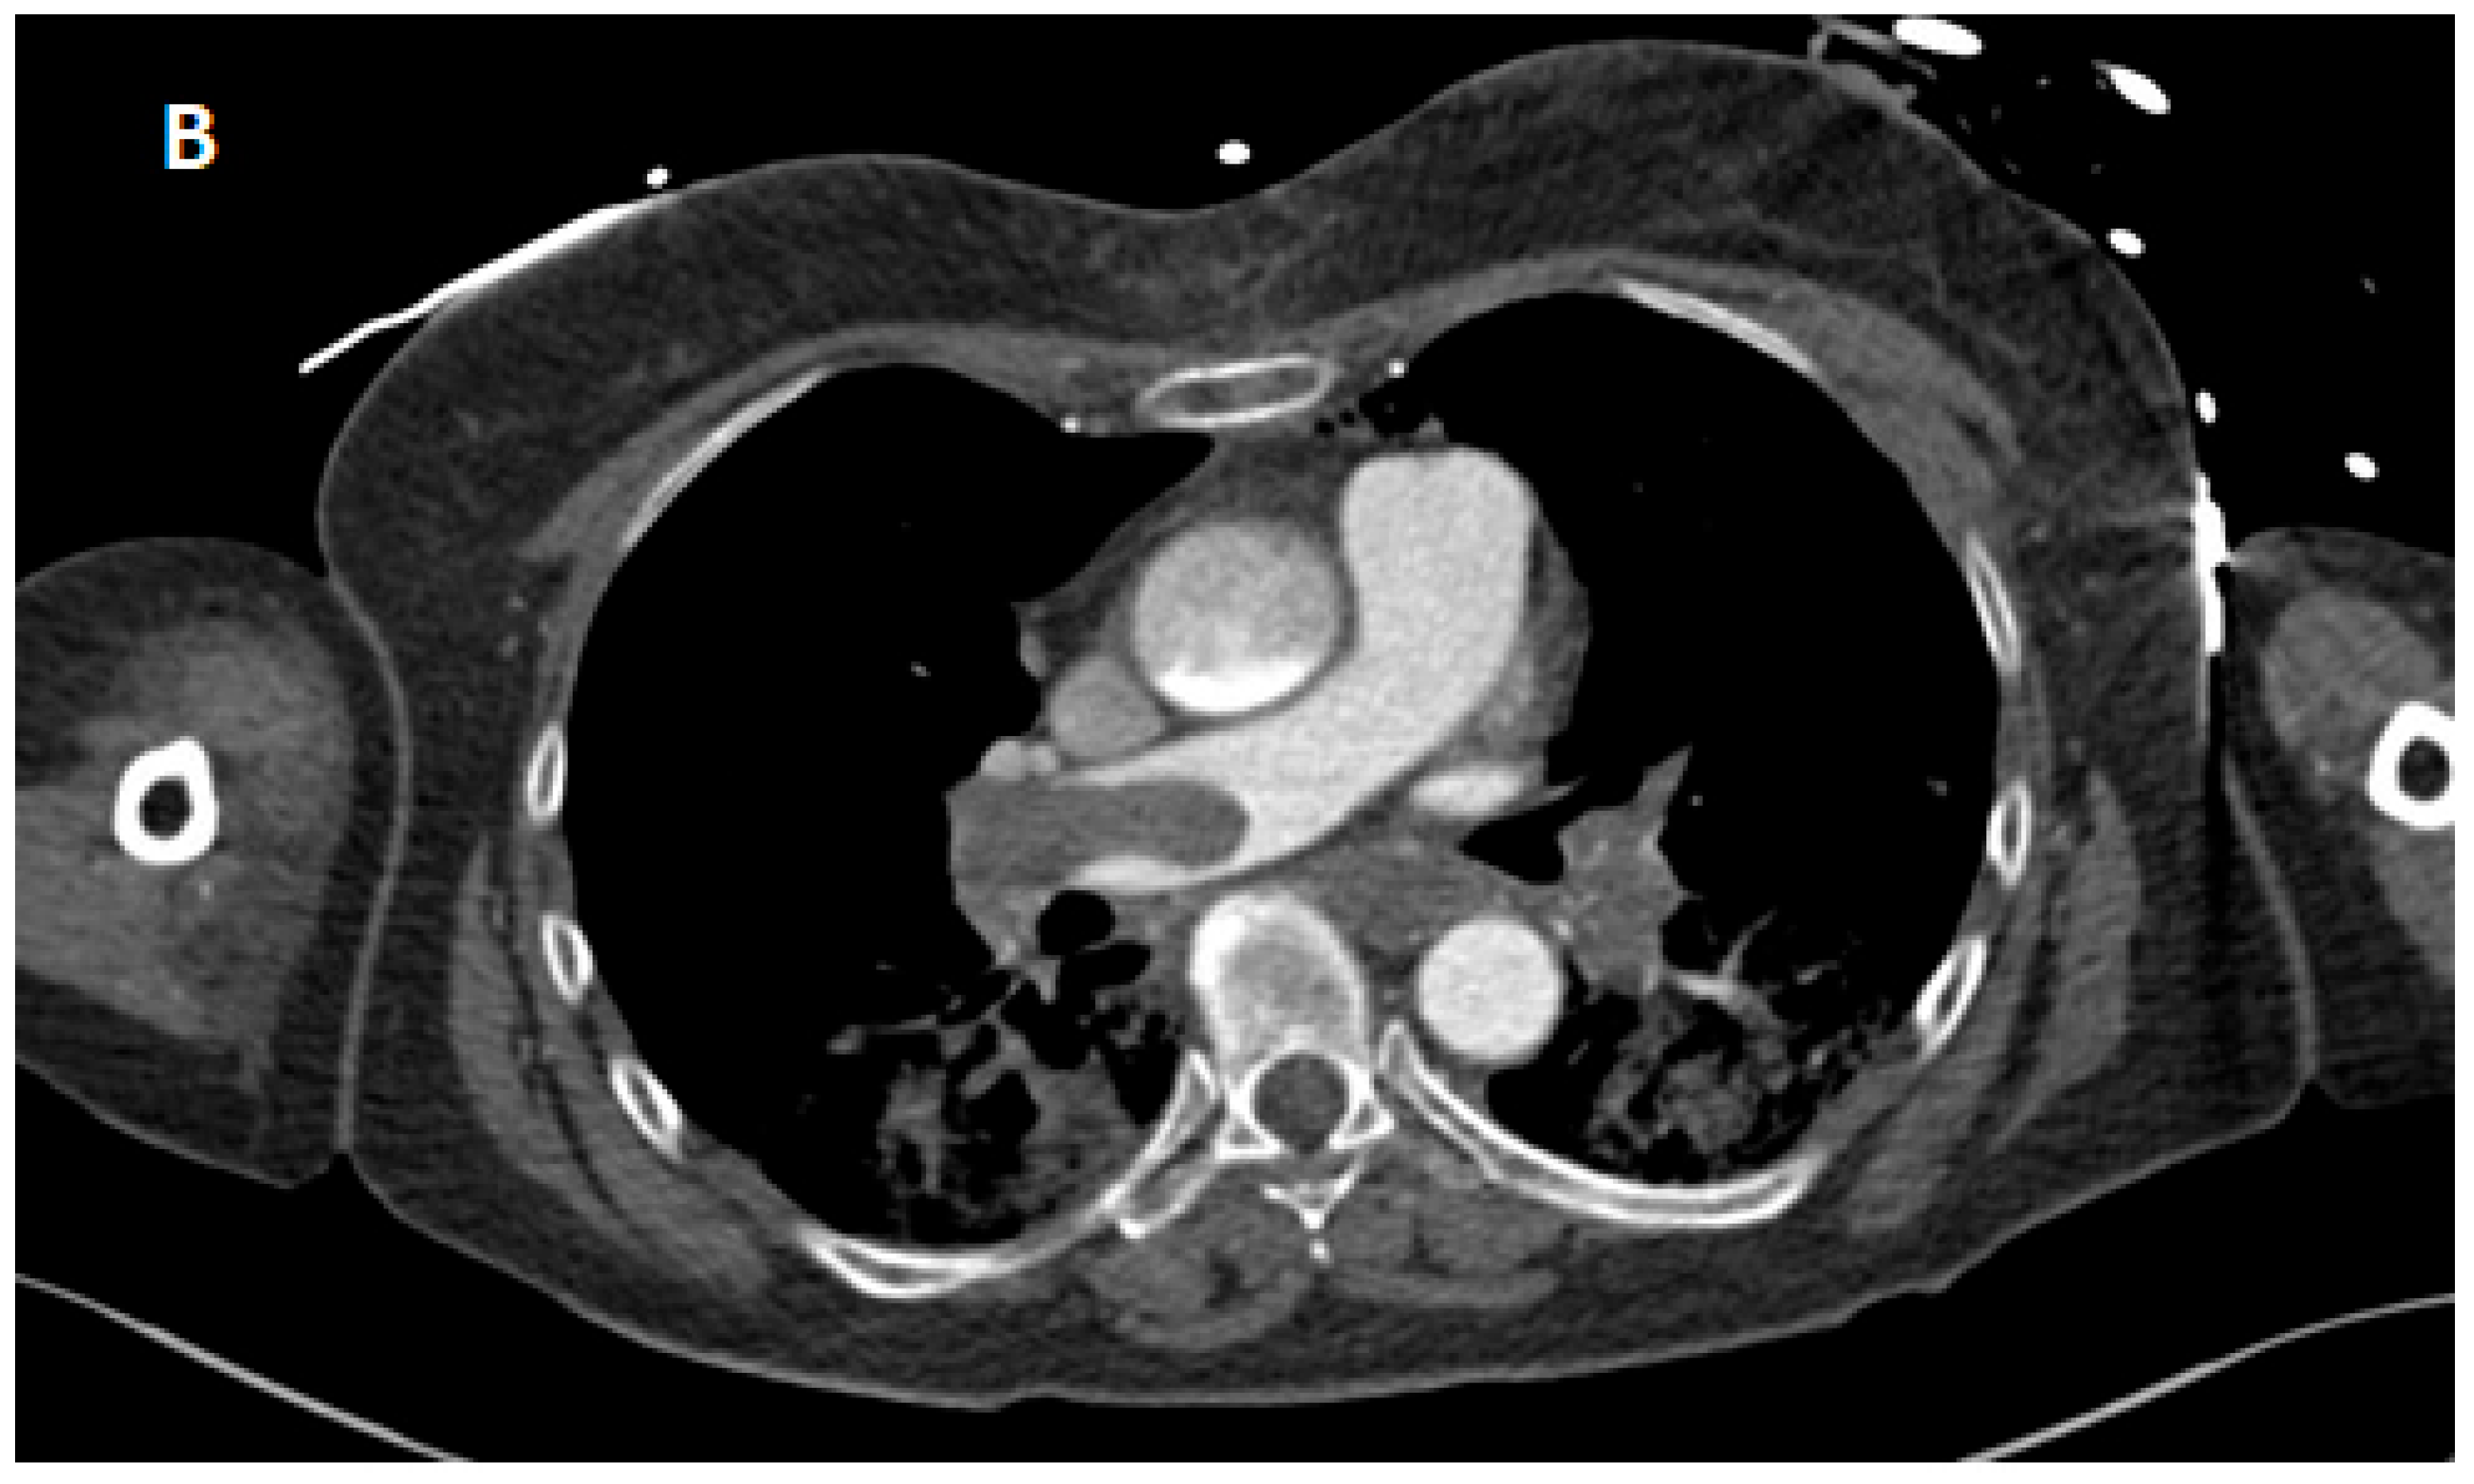

2. Case Presentation